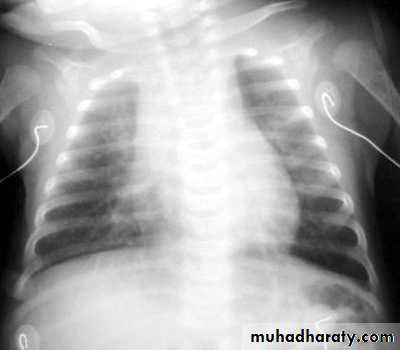

Q8/ A 6-week-old infant arrives with a complaint of “breathing fast” and a cough. On examination you note the child to have no temperature elevation, a respiratory rate of 65 breaths per minute, and her oxygen saturation to be 94%. Physical examination also is significant for rales and rhonchi. The past medical history for the child is positive for an eye discharge at 3 weeks of age, which was treated with a topical antibiotic drug.

CXR chlamydia pneumoniae in infant

Chlamydiae organisms, sexually transmitted among adults, are spread to infants during birth from genitally infected mothers. The sites of infection in infants are the conjunctivae and the lungs, where chlamydiae cause inclusion conjunctivitis and afebrile pneumonia, respectively, in infants between 2 and 12 weeks of age.Diagnosis is confirmed by culture of secretions and by antibody titers.

The most common treatment for this condition includes macrolide antibiotics orally, which clears both the nasopharyngeal secretions when conjunctivitis is present and prevents the pneumonia that can occur later. Topical treatment for chlamydia conjunctivitis is not effective in clearing the nasopharynx. Early treatment with oral macrolides is, however, associated with an increased incidence in the development of idiopathic hypertrophic pyloric stenosis; their use in a neonate is with caution.